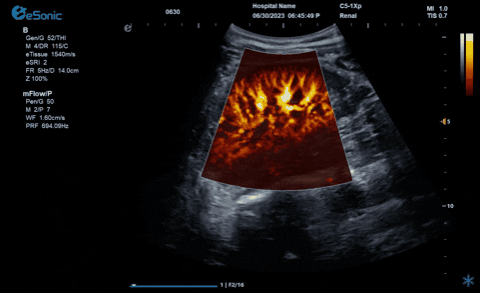

百乐博平台医疗的eHertz系列彩色多谱超声诊断系统凭借强大的RawVision?原数精准平台和SDBeam?软波声束合成技术推出专属的mFlow ?超微血流显像技术,该项技术可专用于极低速血流成像。彩色多普勒血流(CDFI)检查时,通常会将滤波器的频率设置为大约50hz,并随时调整标尺和增益,以便在背景噪声发生前显示小血管......